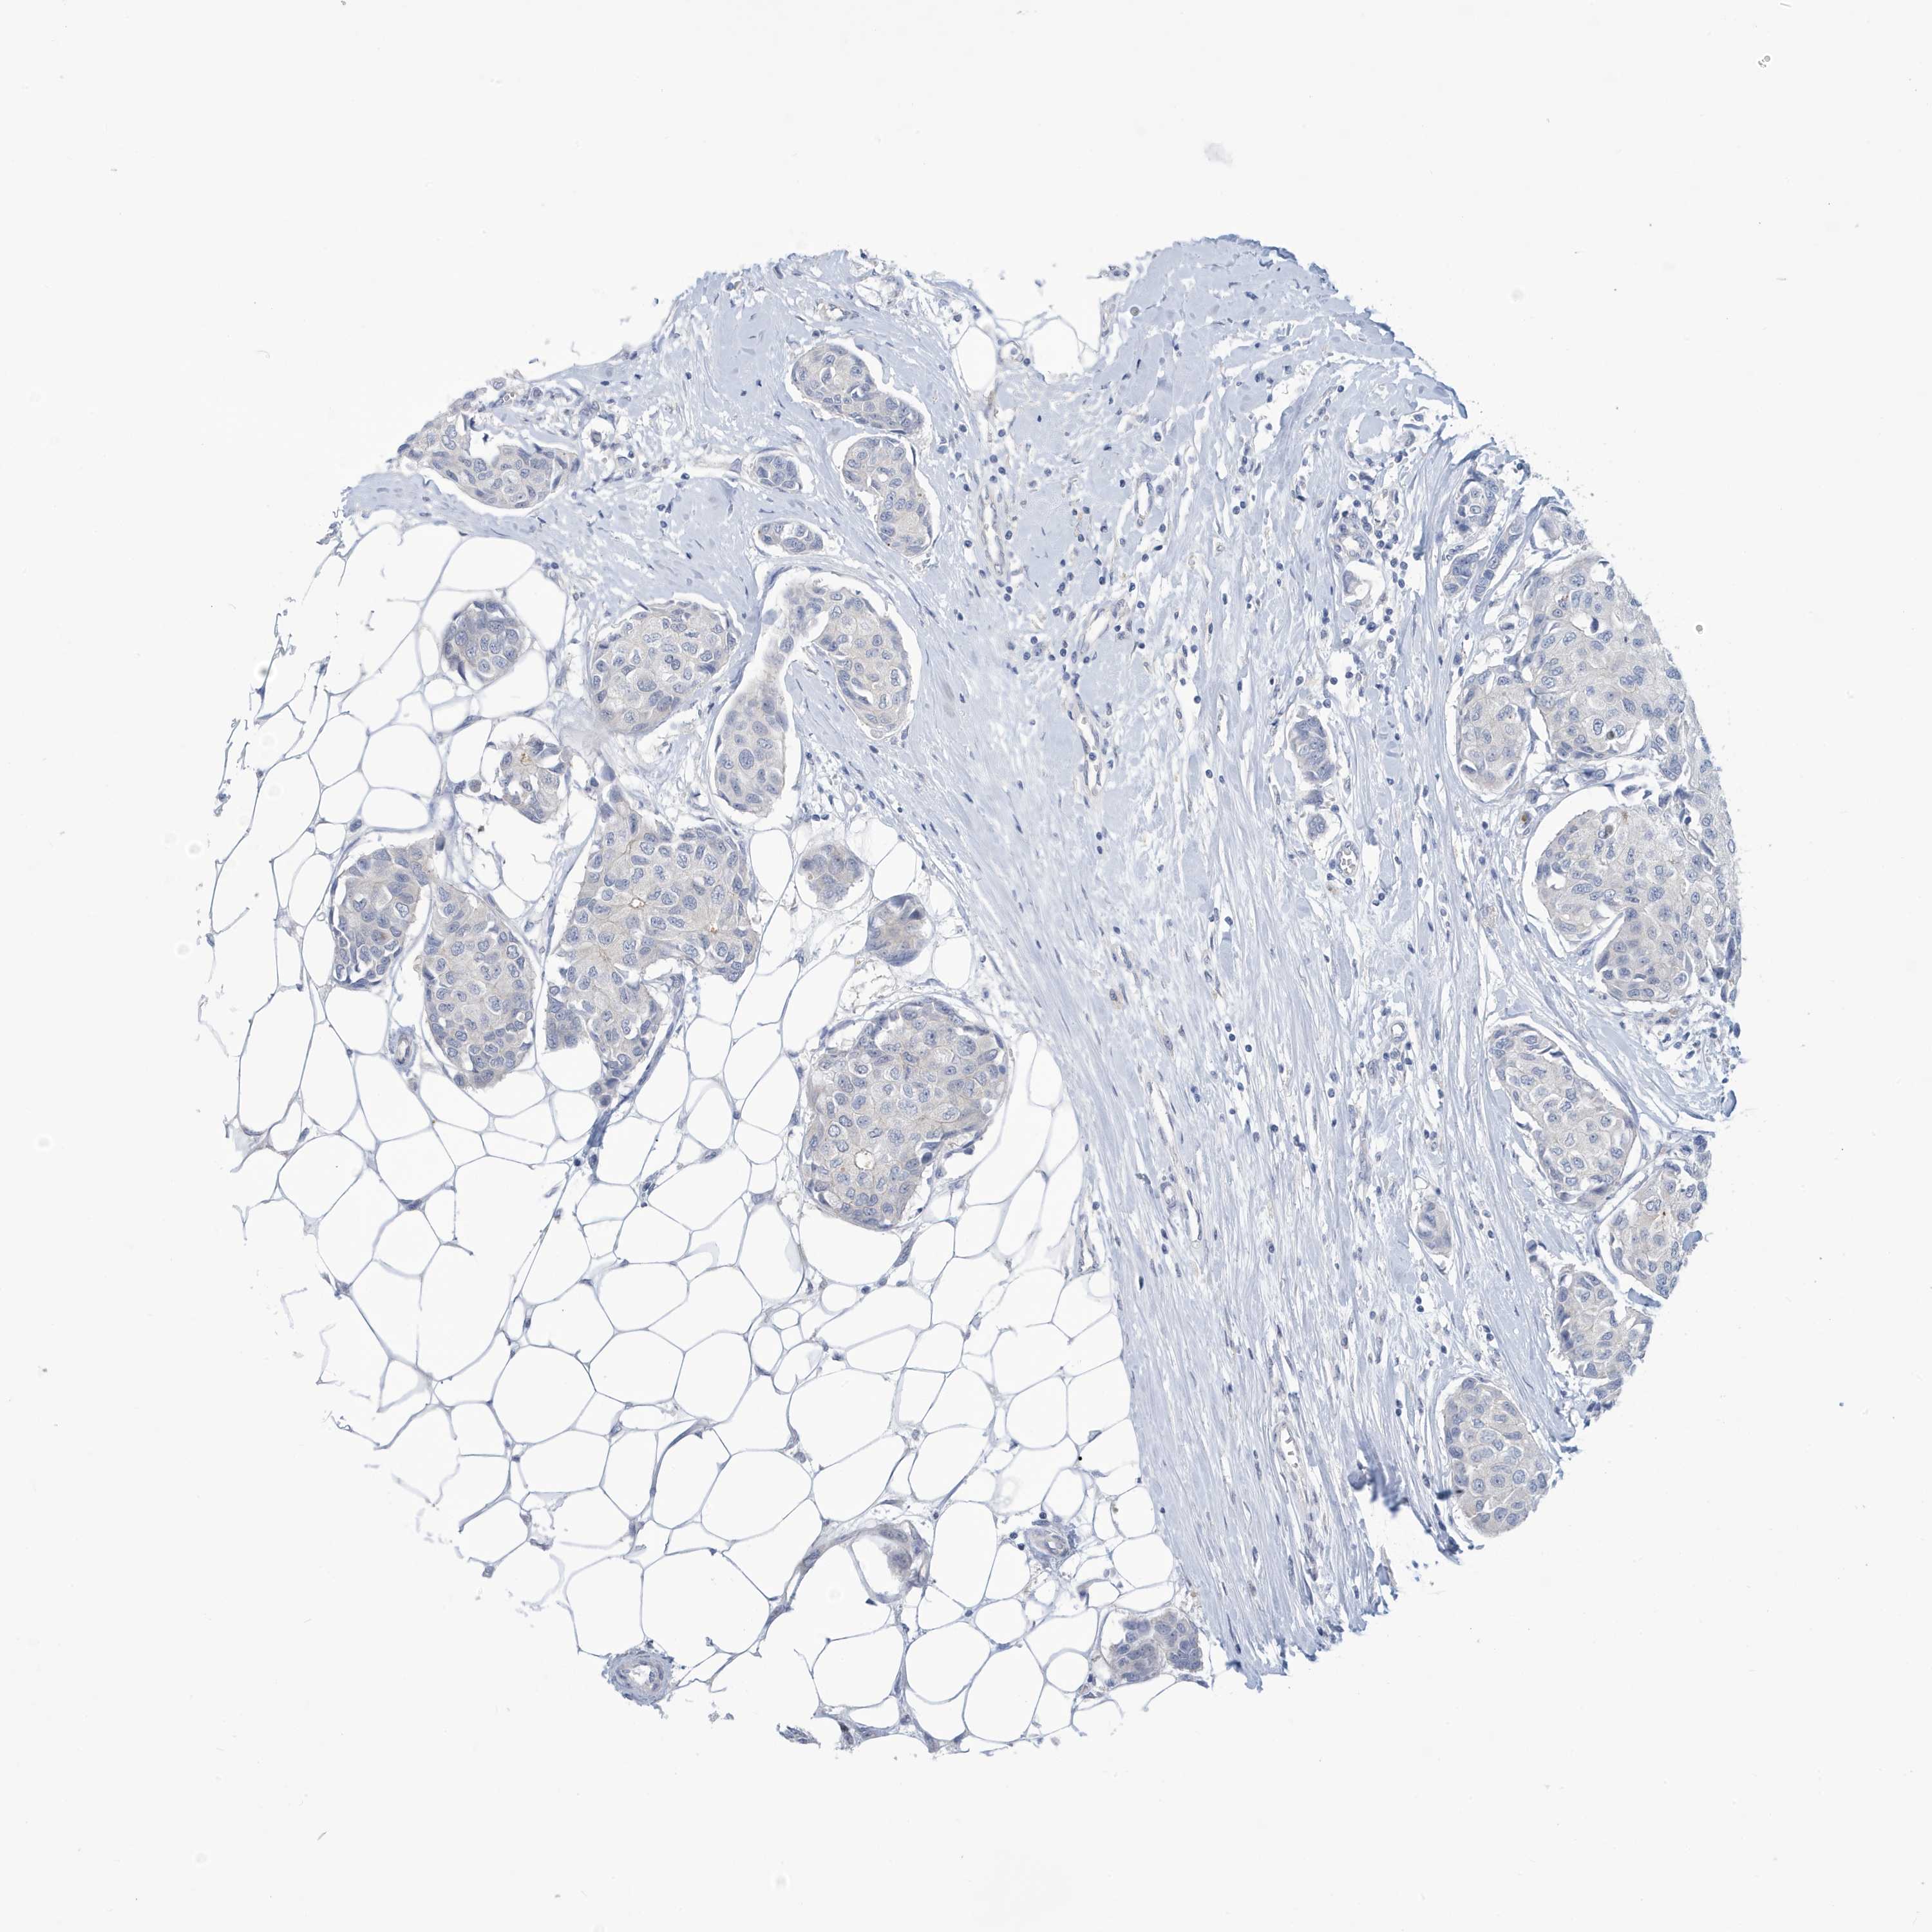

BRCA TCGA BRCA VALIDATION PROTEIN EXPRESSION

ANTIBODIES

AND

VALIDATION